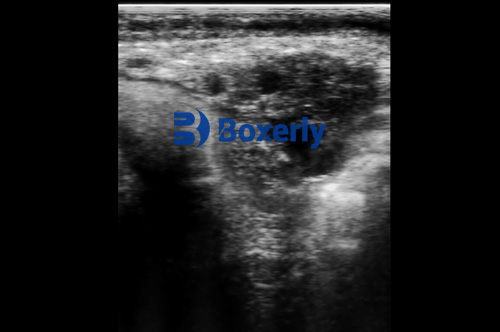

Veterinary ultrasound, particularly B-mode ultrasonography, is a non-invasive, real-time imaging technique that provides visual assessments of soft tissue structures, organs, reproductive tracts, and even muscle and fat distribution in farm animals. Its applications span from pregnancy detection in sows and cows to monitoring uterine recovery and diagnosing internal pathologies.

One of the most critical factors in ultrasound performance is screen clarity. High-resolution imaging is essential for identifying subtle anatomical structures, distinguishing between healthy and abnormal tissue, and confirming pregnancy at an early stage.

Ultrasound users from the UK and Canada frequently report that blurry or low-contrast images can lead to misinterpretation, reducing diagnostic accuracy. Modern machines now offer HD displays with grayscale depths of 256 levels or more. These allow for nuanced visualization of uterine linings, fetal development, and follicular structures.